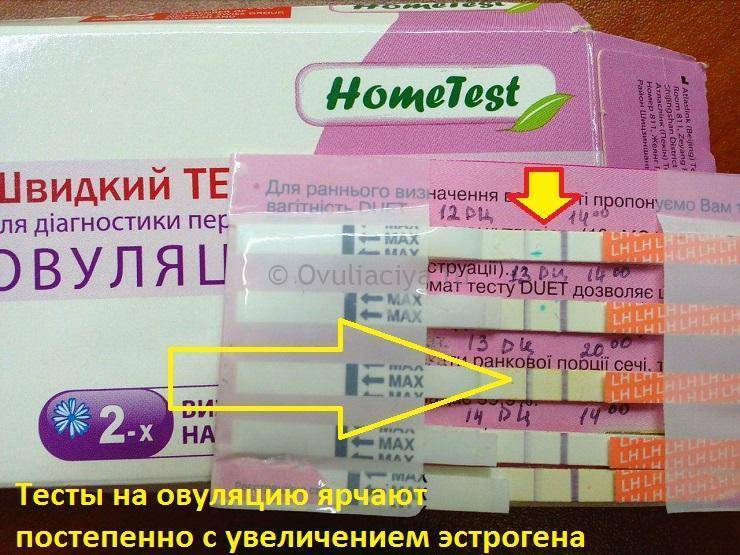

Рекомендации по зачатии